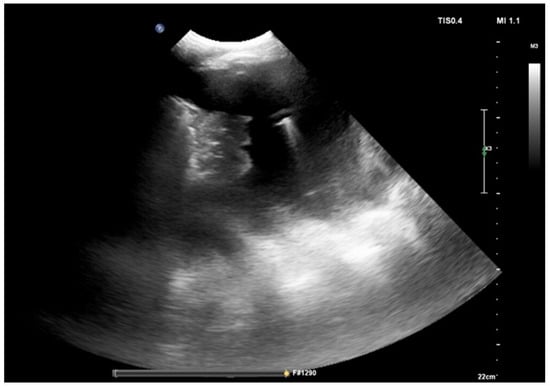

4. Ultrasound-Assisted Procedure

- anechoic (without echoic images);

- complex non-septated (echogenic material is detected inside the effusion);

- complex septated (floating fibrin strands or septs are found inside the effusions);

- homogenously echogenic.